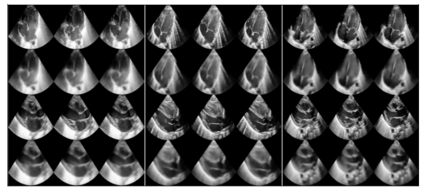

We propose a novel anomaly detection method for echocardiogram videos. The introduced method takes advantage of the periodic nature of the heart cycle to learn different variants of a variational latent trajectory model (TVAE). The models are trained on the healthy samples of an in-house dataset of infant echocardiogram videos consisting of multiple chamber views to learn a normative prior of the healthy population. During inference, maximum a posteriori (MAP) based anomaly detection is performed to detect out-of-distribution samples in our dataset. The proposed method reliably identifies severe congenital heart defects, such as Ebstein's Anomaly or Shonecomplex. Moreover, it achieves superior performance over MAP-based anomaly detection with standard variational autoencoders on the task of detecting pulmonary hypertension and right ventricular dilation. Finally, we demonstrate that the proposed method provides interpretable explanations of its output through heatmaps which highlight the regions corresponding to anomalous heart structures.